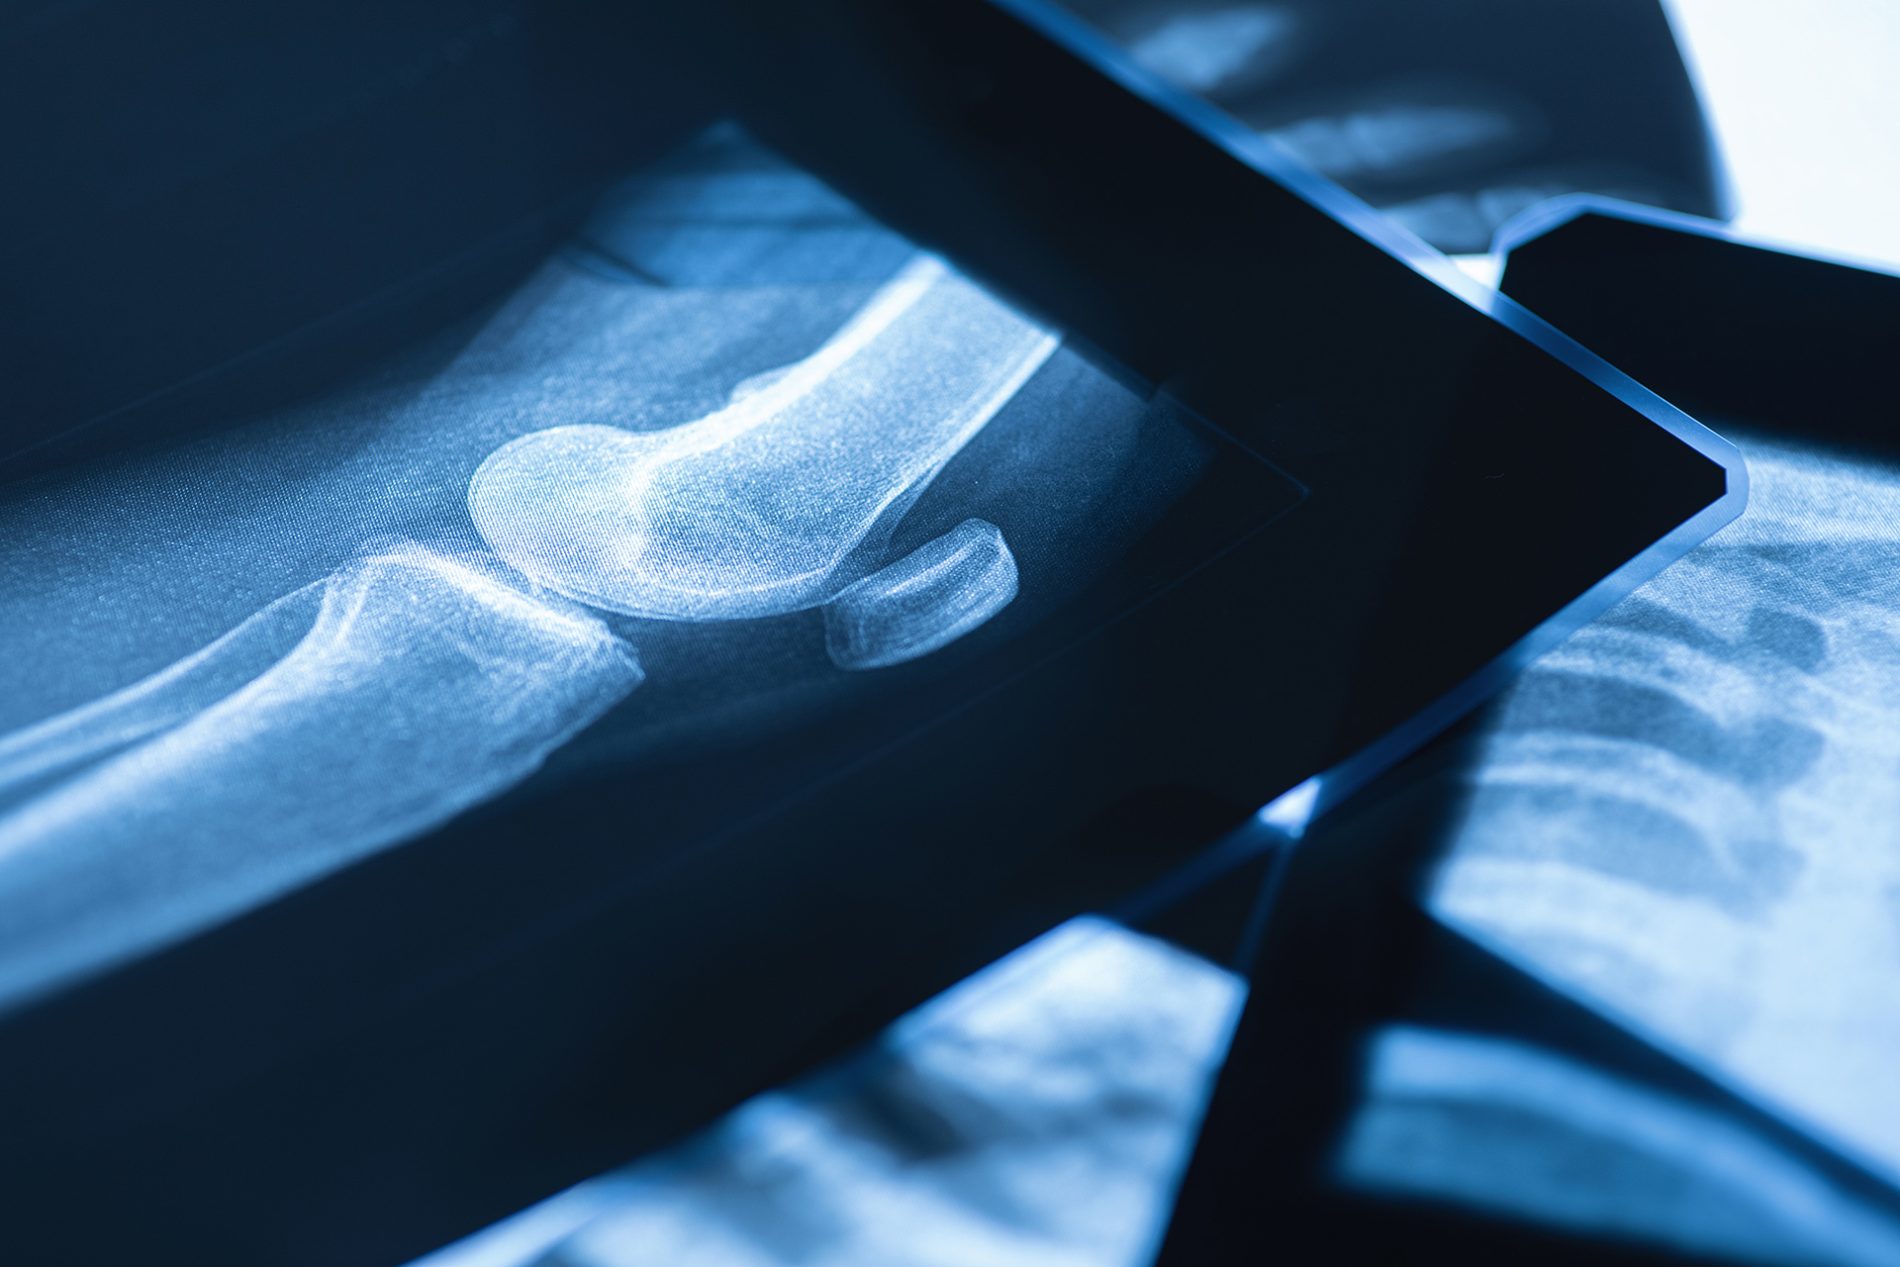

Il reparto di Ortopedia e Traumatologia si occupa della diagnosi e trattamento delle patologie articolari, muscolari e ossee, dai traumi acuti alle degenerazioni croniche.